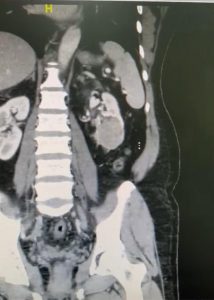

وأفاد بعد استكمال كافة الفحوصات الطبية اللازمة التي بينت نتائجها وجود ورم بحجم 7 سنتميتر في الكِلية اليسرى، حيث اتضح وجود الورم في معظم الكِلية اليسرى للمريض، الأمر الذي استدعى تحضير المريض لنقله إلى قسم العمليات، حيث تقرر التدخل العاجل لإجراء عملية نوعية دقيقة بالمنظار الجراحي.